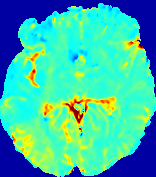

LesionRefer to captionRefer to captionRefer to captionRefer to captionRefer to captionRefer to caption𝐕rgbsubscript𝐕𝑟𝑔𝑏{\bf{V}}_{rgb}Refer to captionRefer to captionRefer to captionRefer to captionRefer to captionRefer to caption𝐕2subscriptnorm𝐕2{\|\bf{V}}\|_{2}Refer to captionRefer to captionRefer to captionRefer to captionRefer to captionRefer to captionRefer to caption3.53.53.52.82.82.82.12.12.11.41.41.40.70.70.70.00.00.0(mm/s)𝑚𝑚𝑠(mm/s)D𝐷DRefer to captionRefer to captionRefer to captionRefer to captionRefer to captionRefer to captionRefer to caption0.0200.0200.0200.0160.0160.0160.0120.0120.0120.0080.0080.0080.0040.0040.0040.0000.0000.000(mm2/s)𝑚superscript𝑚2𝑠(mm^{2}/s)Slice #1Slice #2Slice #3Slice #4Slice #5Slice #6

Figure 4: PIANO feature maps for another patient in the ISLES 2017 training set, where the lesion is located in the right hemisphere. Top row: segmented stroke lesion region (white) on different slices. The corresponding slices for the PIANO feature maps are shown in the following rows.

For a better insight into an estimated velocity field 𝐕𝐕{\bf{V}} and diffusion field 𝐃𝐃{\bf{D}}, we compute the following maps: (1) 𝐕rgbsubscript𝐕𝑟𝑔𝑏{\bf{V}}_{rgb}: Color-coded orientation map of 𝐕=(Vx,Vy,Vz)T𝐕superscriptsuperscript𝑉𝑥superscript𝑉𝑦superscript𝑉𝑧𝑇{\bf{V}}=(V^{x},V^{y},V^{z})^{T}, obtained by normalizing 𝐕𝐕{\bf{V}} to unit length and mapping its 3 components to red, green, blue respectively; (2) 𝐕2subscriptnorm𝐕2\|{\bf{V}}\|_{2}: 222 norm of 𝐕𝐕{\bf{V}}; (3) D𝐷D: scalar field in Eq. 5.

Fig. 3 and Fig. 4 show the PIANO feature maps estimated from two ISLES 2017 patients: all are highly consistent with the lesion in both cases. Details of the blood flow trajectories are revealed in 𝐕rgbsubscript𝐕𝑟𝑔𝑏{\bf{V}}_{rgb} by the ridged patterns and the sharp changes of colors in the unaffected (right) hemisphere, while the flat patterns appearing within the lesion provide little directional information about the velocity and indicate low velocity magnitudes. Velocity magnitudes are more directly visualized via 𝐕2subscriptnorm𝐕2\|{\bf{V}}\|_{2}, from which one can easily locate the lesion where 𝐕2subscriptnorm𝐕2\|{\bf{V}}\|_{2} is low. D𝐷D also indicates lower diffusion values in the lesion, though with less contrast potentially due to the fact that it captures the accumulated effect of CA diffusion at the voxel-level.